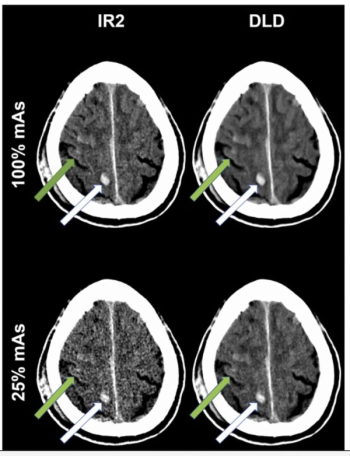

For patients who had neuroradiological trauma CT scans, researchers noted no significant visual differences between deep learning denoising at 25% mAs and iterative reconstruction at 100% mAs.